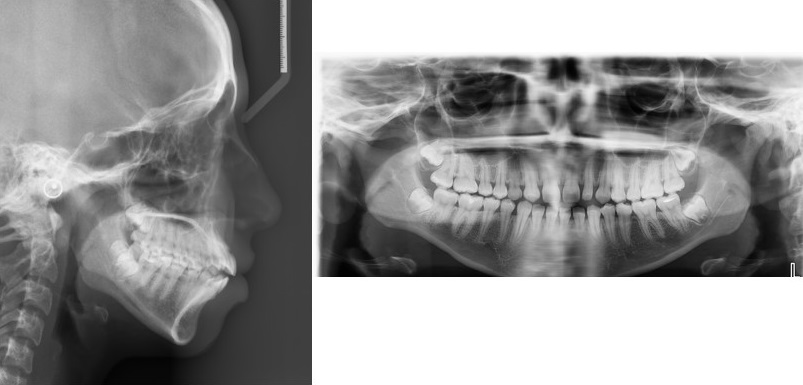

In our study, 15.24% had the presence of at least one DA. Our study included the entire spectrum of DA (Figs. 3-5). The results of our study demonstrated an increased frequency of type II and III STB (complete calcification) in patients with DA, which was statistically significant when compared to the control group. Previous studies reported the incidence of STB that ranged from 9.67 to 25.8 in patients with buccal and palatal impacted canines [11-13], 6 to 21.7% in patients with hyperdontia, 23.8% in patients with dental transposition [14], 15 and 18.7% in patients with agenesis [2], 13.3% in patients with highly placed canines [15] and 14.3% and 16.7% in patients with palatally displaced canines [2, 9].